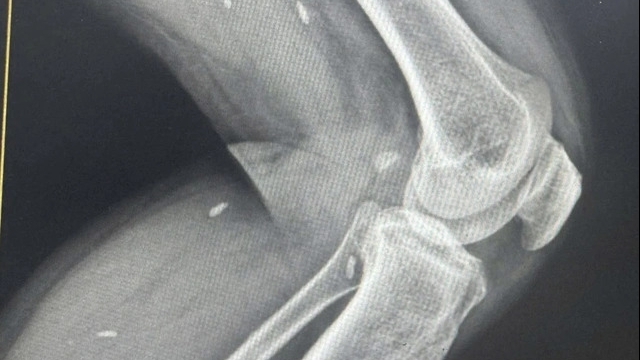

Sau khi thăm khám, các bác sỹ tại bệnh viện phát hiện phần vách ngăn mũi bị vẹo và bị viêm mũi xoang. Để xác định rõ nguyên nhân gây ra triệu chứng đau đầu, các bác sỹ đã tiến hành nội soi, chụp Xquang.

Từ hình ảnh, các bác sĩ phát hiện ở vị trí xoang sàng sau bên trái, sát nền sọ. Nghi ngờ một răng lạc chỗ, bệnh viện đã yêu bệnh nhân ở lại viện tiếp tục theo dõi, đồng thời lên lịch phẫu thuật cho người này.